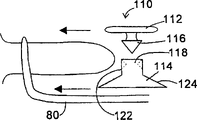

- A61B17/70—Spinal positioners or stabilisers, e.g. stabilisers comprising fluid filler in an implant

- A61B17/7062—Devices acting on, attached to, or simulating the effect of, vertebral processes, vertebral facets or ribs ; Tools for such devices

- A61B17/7065—Devices with changeable shape, e.g. collapsible or having retractable arms to aid implantation; Tools therefor